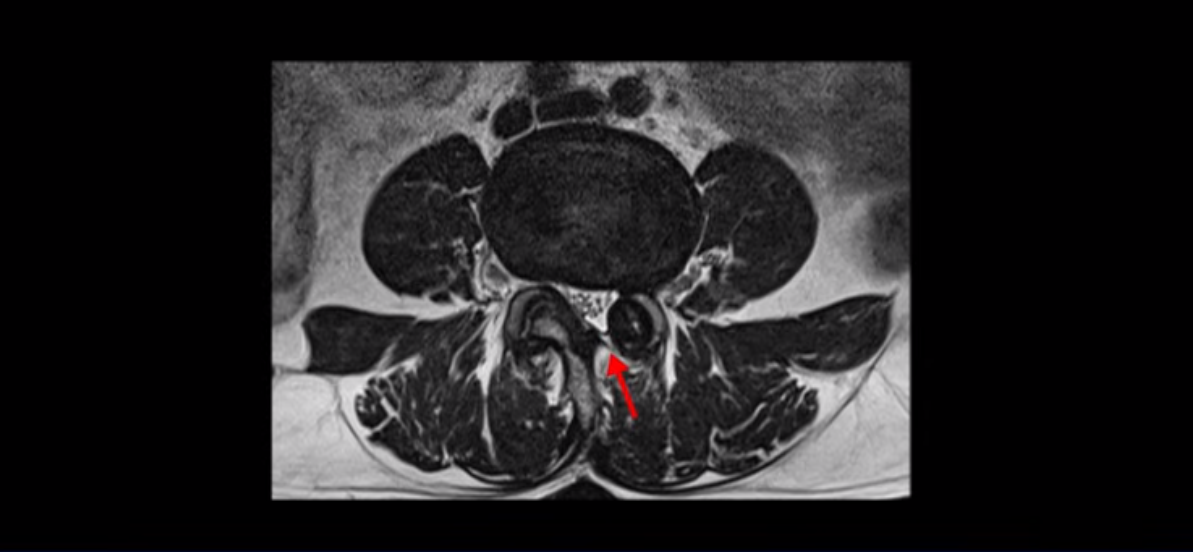

단면으로 보면 왼쪽 후궁을 제거한 흔적이 보입니다.

5번 1번도 왼쪽 후궁을 열고 수술 받았습니다.

하지만 중심성 협착은 여전히 심한 상태입니다.

이분은 오른쪽, 왼쪽 다리에 모두 방사통이 심하고 왼쪽 다리에 마비 증상, 즉 풋드랍(족하수) 증상이 있습니다. 왼쪽 신경 가지가 빠져나가는 추간공을 보면 두 마디가 좁아져 있습니다.

이런 신경 구멍이 좁아져 있는 걸 협착이라고 합니다.